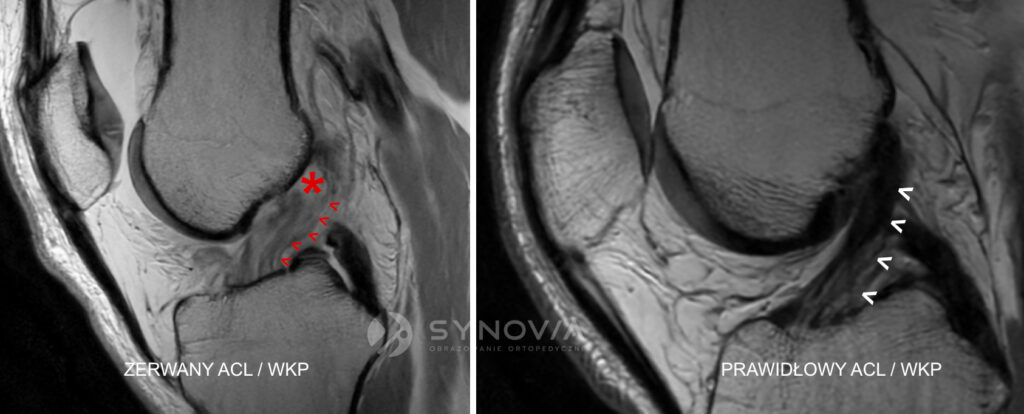

Więzadło krzyżowe przednie (ACL/WKP) – 15–20% wszystkich kontuzji narciarskich

To najpoważniejsza i najbardziej znana kontuzja narciarzy.

Klasyczny mechanizm to „phantom foot” – tylny koniec narty zostaje zahaczony o śnieg, a kolano obraca się do wewnątrz przy obciążonej nodze. Narta działa jak długa dźwignia, która potęguje rotację.

Diagnostyka:

- USG – częściowa ocena, przydatna głównie w ocenie obrzęków, wysięków, urazów towarzyszących

- MRI – złoty standard: ocena ciągłości, stopnia uszkodzenia, współistniejących urazów łąkotek, chrząstki i pozostałych więzadeł.